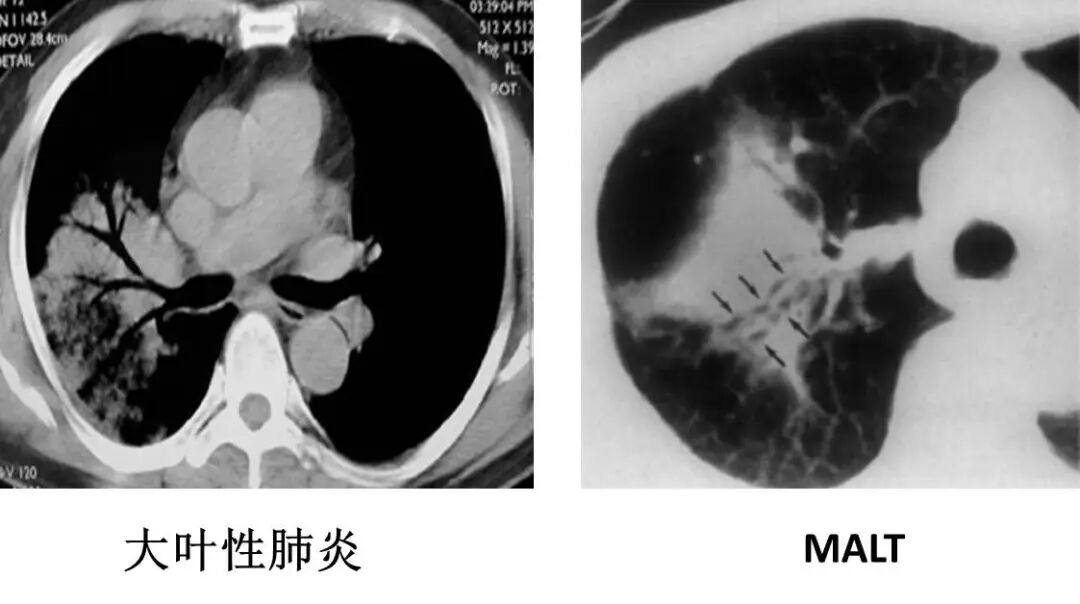

大叶性肺炎

临床症状:高热,咳嗽,咳铁锈色痰;

白细胞总数及中性粒细胞增高 ;

肺段/肺叶分布,片状实变影;

充气的支气管管径、形态均正常。

肺粘膜相关淋巴瘤

结节、肿块,边缘模糊

充气支气管粗大、扭曲

临床症状明显

充气的支气管管径、形态正常